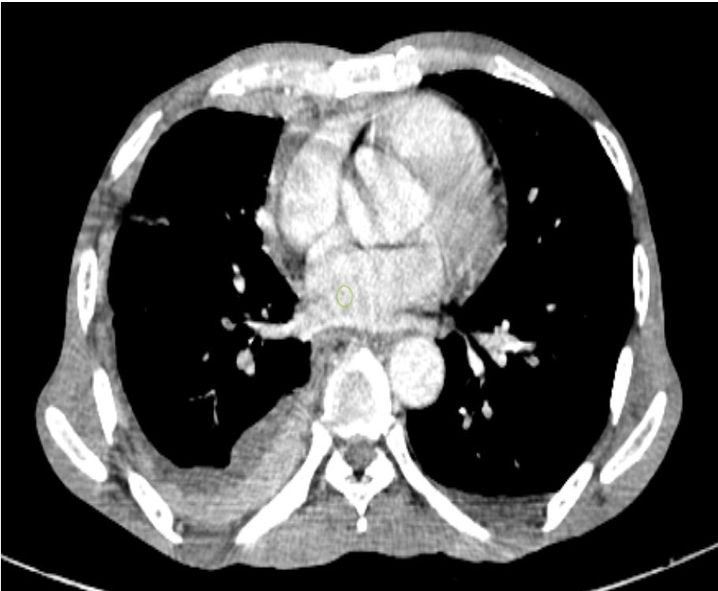

USG Neck-Thyroid gland appears normal in size and texture. No evidence of enlarged Parathyroid glands. No other significant abnormality detected CECT Thorax and abdomen-Image shows pleural thickening with enhancement

(costal, mediastinal and diaphragmatic pleura).

Above findings give a differential diagnosis of Koch’s Disease or Mesothelioma to be considered and suggested pleural biopsy(image enclosed) Histopathology of pleura(CT guided pleural biopsy)- Section studied show thickened pleura with numerous granuloma composed of epithelioid cells, Langhan’s giant cells and few lymphocytes-features are suggestive of tuberculosis of pleura Final diagnosis-